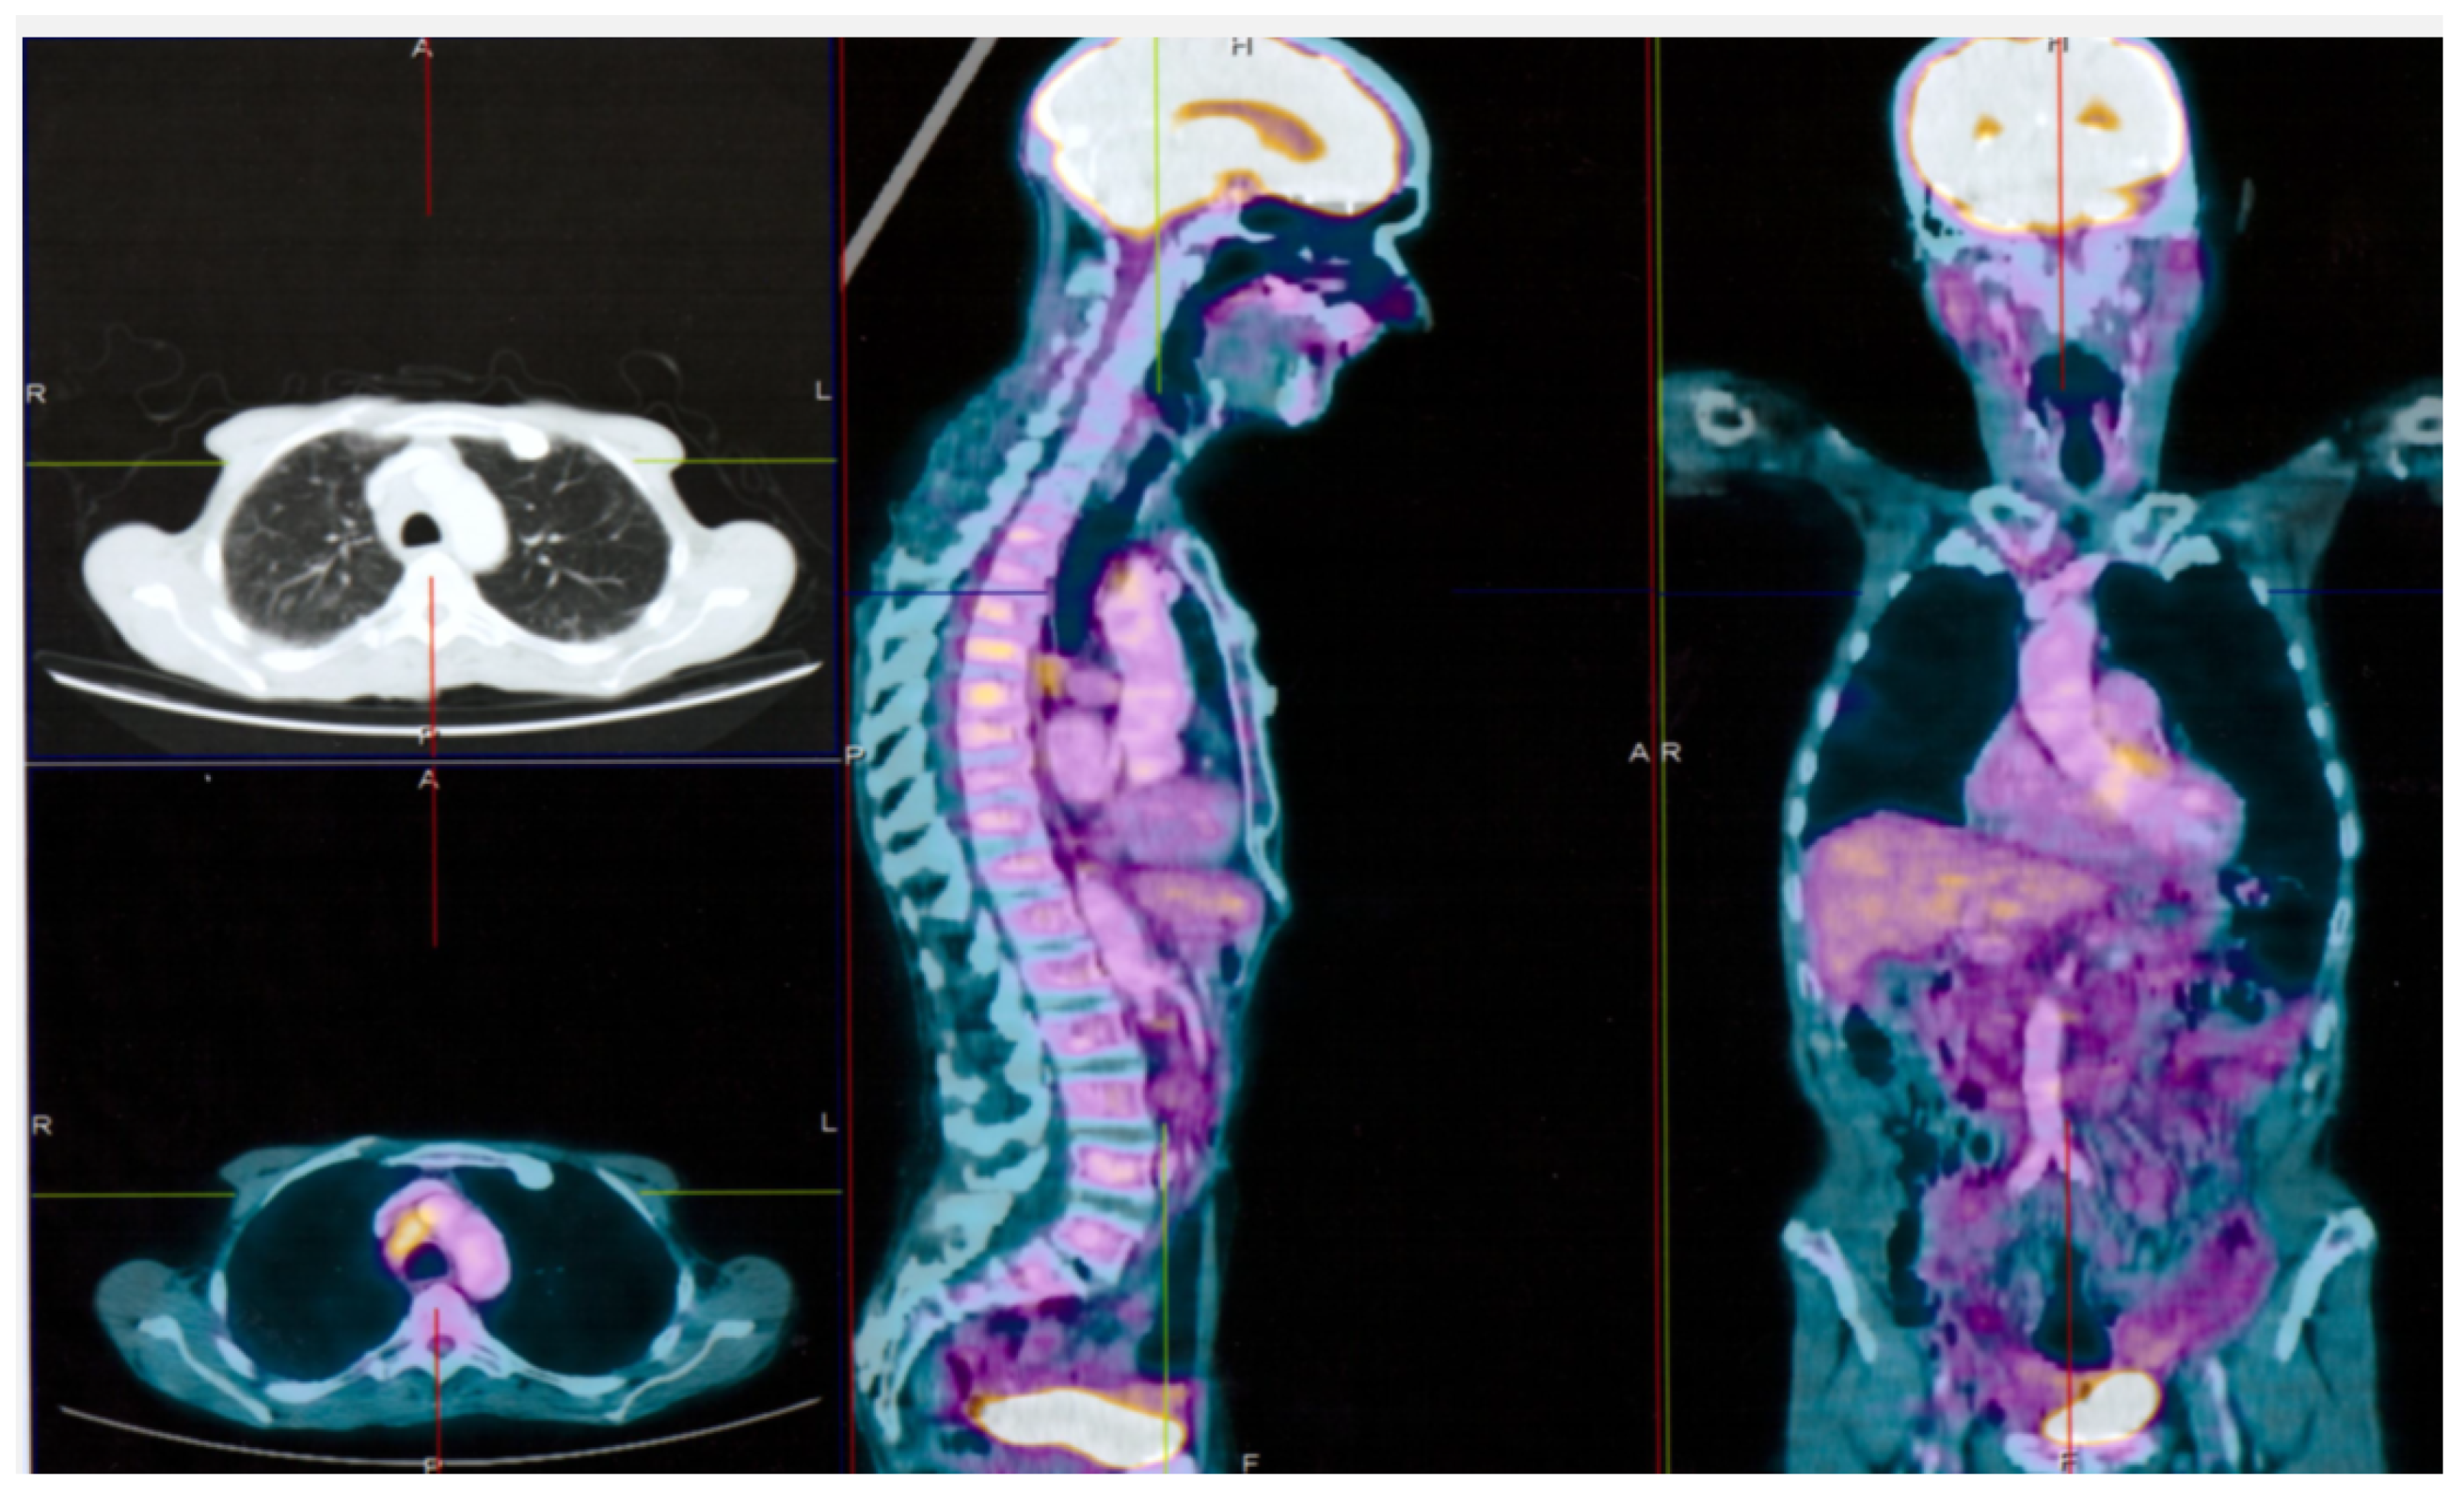

2. Case Report